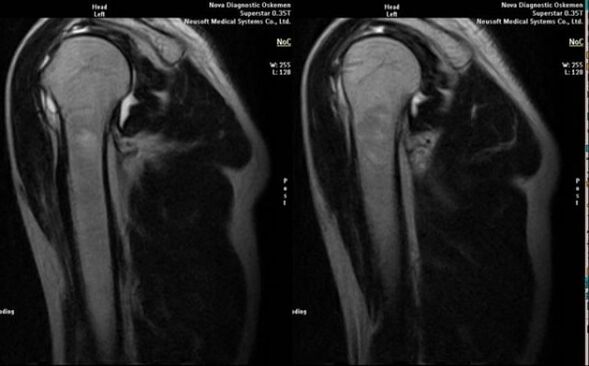

- MRI and CT scan;

Signs that directly indicate the development of osteoarthritis include the appearance of a significant narrowing of the joint space, sclerosis of subcartilaginous structures, thinning of the chondrocyte layer itself, the appearance of osteophytes and the deposition of salt crystals in the intra-articular fluid.